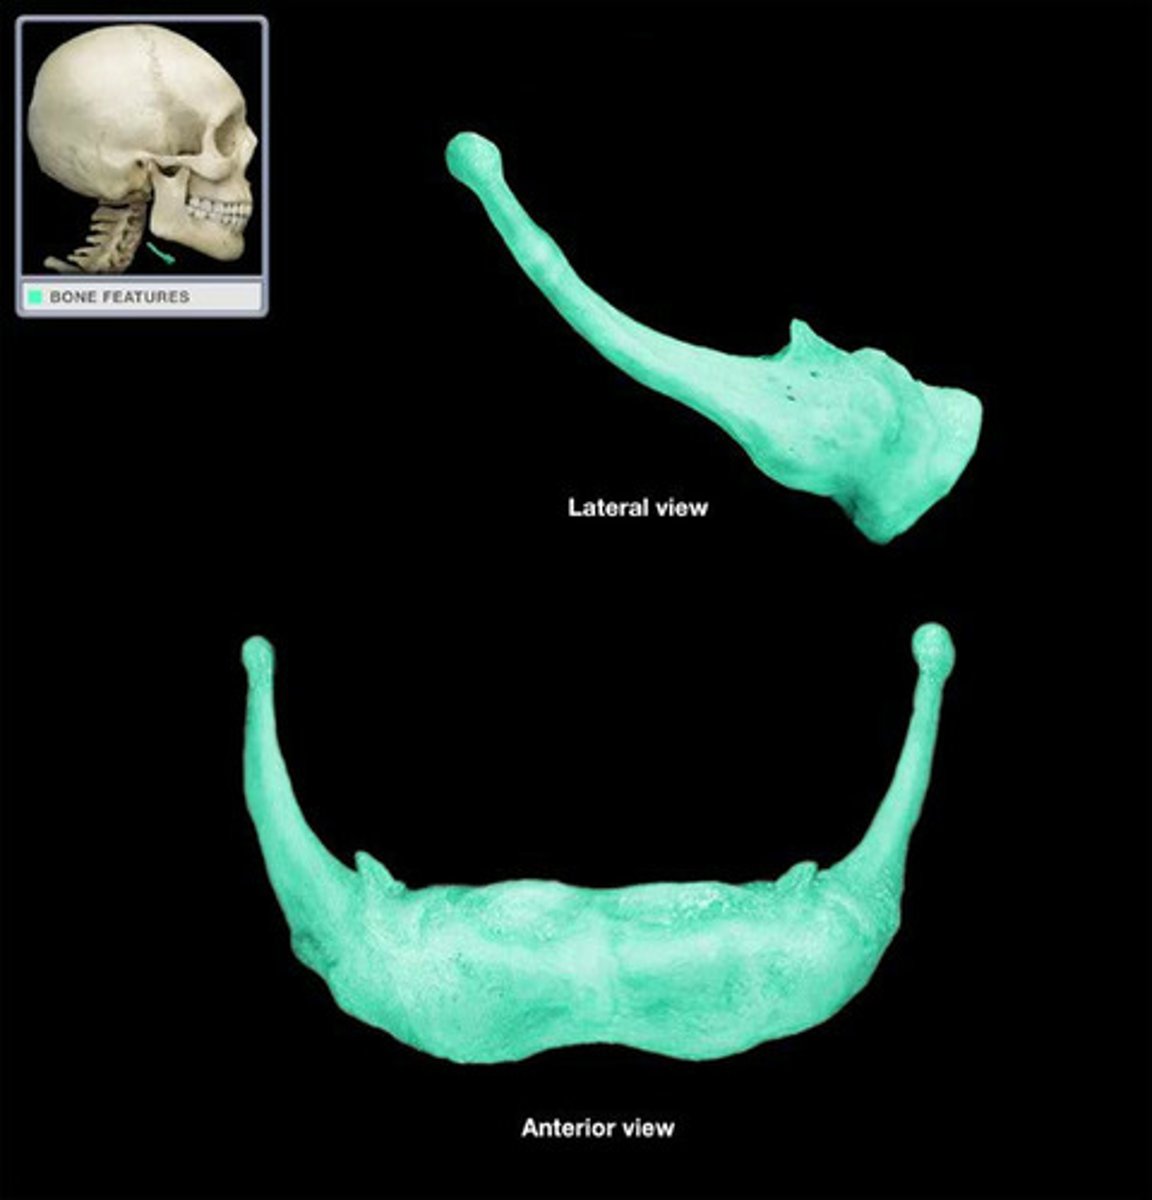

Mandible

Body

name this region

Ramus

Mental Foramen

Angle

...

Mandibular foramen

...

Mandibular Condyle

...

Mandibular notch

...

Coronoid process

...

Alveolar processes

...

Incisive foramen

...

Alveolar processes

...

infraorbital foramen